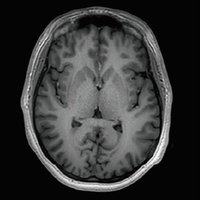

Der Vantage Galan 3T von Canon Medical Systems bietet Ihnen und Ihren Patienten eine neuartige Erfahrung in der Magnetresonanztomographie. Der Vantage Galan 3T legt sein Augenmerk auf das positive Patientenerlebnis, eine hohe Bildqualität und einfache klinische Arbeitsabläufe.

KI-optimiertes Arbeiten und modernste 3T-Technologie machen den Vantage Galan 3T von Canon Medical aus. Canons KI-Anwendung AiCE, kurz für Advanced intelligent Clear-Imagequality Engine, entfernt intelligent das Rauschen und führt zu einer Verbesserung des SNR (Signal-Rausch-Verhältnis). Mit Hilfe der Deep Learning Technologie gelingen besonders klare und deutliche Bilder. Insgesamt ermöglicht die KI-Unterstützung des Vantage Galan 3T somit nicht nur eine höhere Auflösung der Bilder, sondern verkürzt in vielen Fällen auch die Aufnahmezeit.

Mit der PURERF-Technologie und der PUREGradienten-Technologie werden das SNR um bis zu 20% verbessert und Diffusionsbilder optimiert.